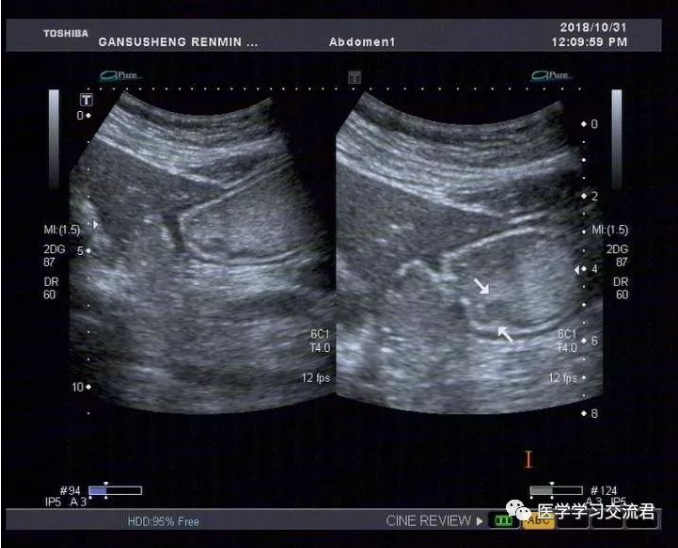

嘱患者饮胃肠造影剂1000ml后扫查:胃贲门及幽门造影剂通过顺畅,胃窦后壁胃壁局限性不均匀增厚,累计长度约19.8mm,最厚处7.4mm,粘膜面连续性中断,可见6mm粘膜凹陷,其内见强回声斑附着,粘膜下层连续完整,局部胃蠕动僵硬,造影剂通过顺畅,余胃壁各层次清楚,粘膜光滑连续,蠕动良好,未见明显肿块及溃疡灶,十二指肠球部充盈好,内未见异常回声。

诊断:胃窦后壁胃壁局限性不均匀增厚并溃疡形成

(早期胃MT?或其他?)

根据2010年国际抗癌联盟/美国癌症联合委员会ICC/AJCC)TNM 分期标准并结合正常胃壁声像图表现得出超声下T分期标准:T1—病变局限于胃壁前三层(强—弱—强)回声线,未突破第三层强回声线;T2—病变侵及胃壁第四层弱回声线,但尚未突破该层结构;T3—病变侵及第五层强回声线但尚未中断;T4—病变突破第五层强回声线,甚至侵犯胃周组织。早期胃癌超声造影图像主要表现为:病变处胃壁局限性不均匀性增厚,回声减低,稍隆起于胃腔内或呈浅凹陷,局部胃壁黏膜层和黏膜肌层破坏、层次不清,与周围正常黏膜界限不清,黏膜表面不光滑或粗糙不平,有时可出现浅而大的黏膜凹陷,深可达黏膜下层,凹陷周缘胃壁水肿增厚,凹陷底部较宽而平,表面常附有不规则强回声斑,病变处胃壁蠕动减弱,局部有僵硬感。

该病例病灶浸润深度仅局限于胃壁的黏膜层或黏膜肌层,黏膜下层连续完整,与良性溃疡性病变在影像学诊断上有一定交叉重叠性,故需仔细甄别且须结合胃镜活检后的最终病理结果。